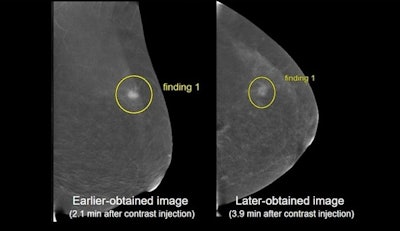

The researchers found that earlier-obtained images had an average acquisition time of 2.5 minutes, compared with 4.75 minutes seen for later-obtained images. In 35 of 390 instances (9%), an individual reader changed the reported lesion type between earlier and later imaging. Of the 35 instances, 28 reflected a situation where a finding was downgraded to a less conspicuous finding on later-obtained imaging.

The team also found that most readers preferred earlier-obtained images when evaluating the visibility of cancer, confidence in margins, and conspicuity of lesion against BPE (p < 0.001). Additionally, most readers preferred craniocaudal views over mediolateral oblique projection when assessing lesion conspicuity against BPE (p = 0.045). The researchers also reported no significant preference for evaluating lesion visibility (p = 0.078) or confidence in margins (p = 0.35).